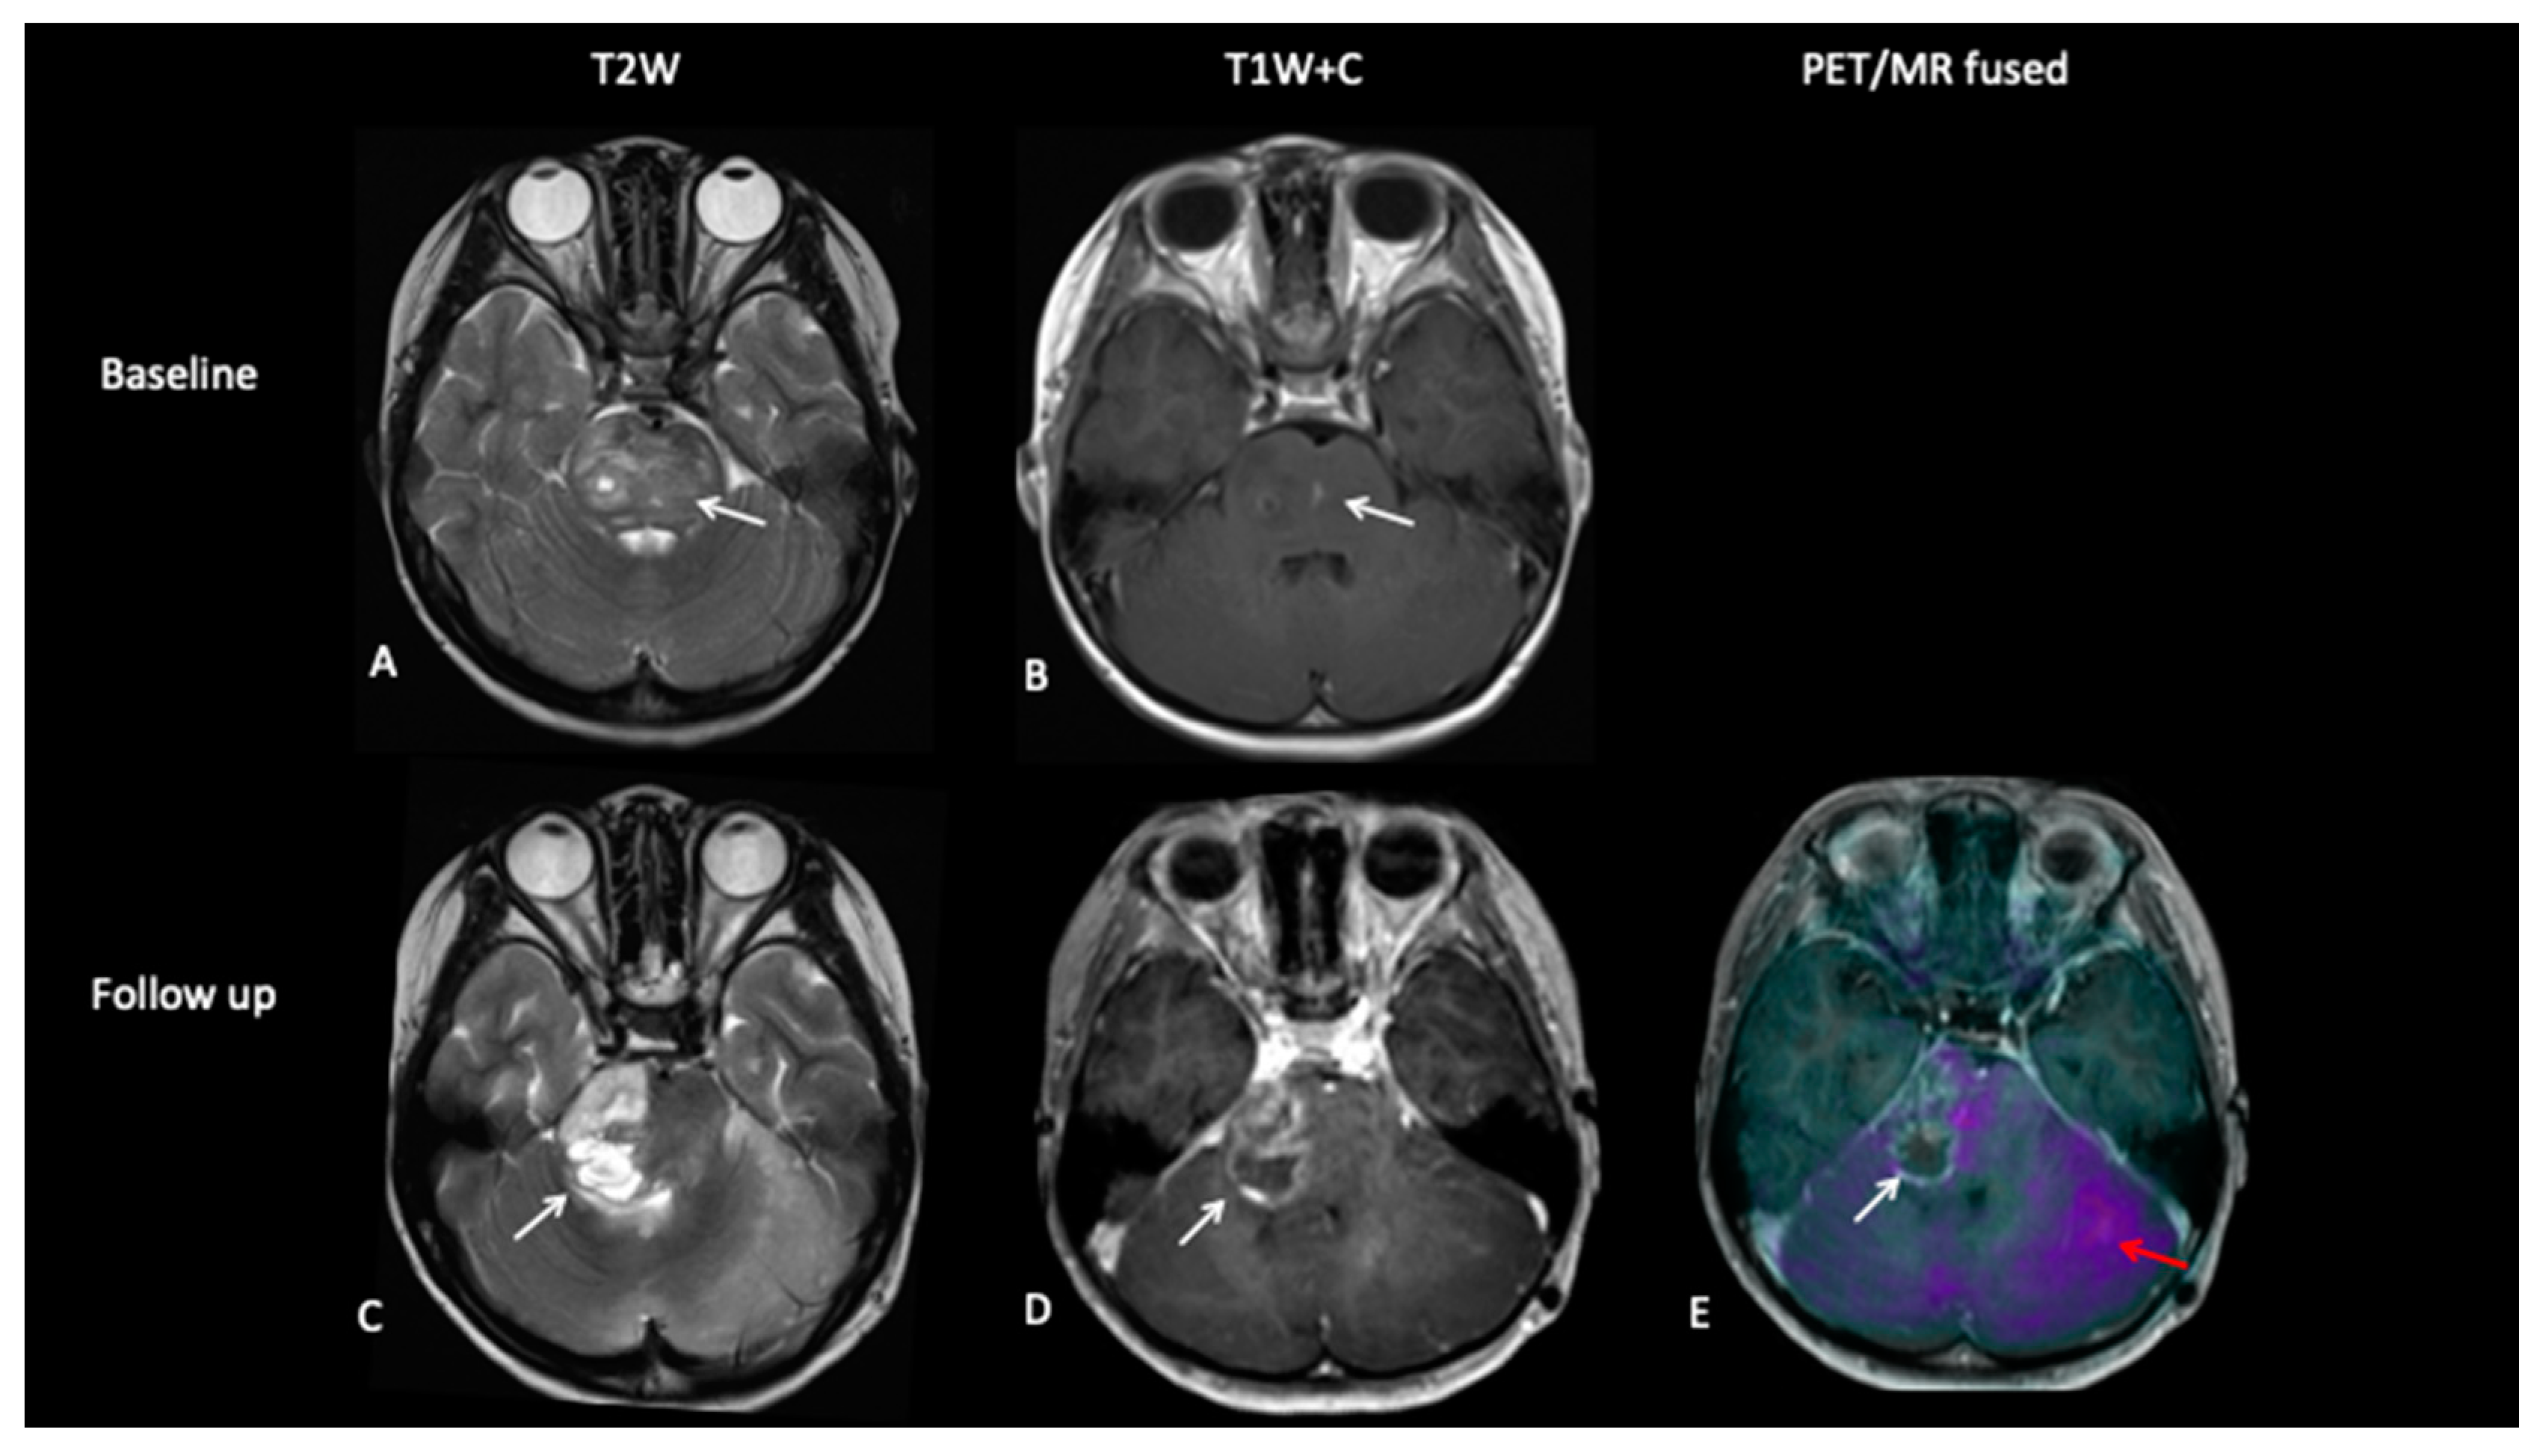

A 5-year-old female with diffuse midline glioma (DMG) presented with a short history of headaches, difficulty in walking and double vision. Radiology at diagnosis was consistent with diffuse intrinsic pontine glioma (DIPG). She commenced on 6 week course of focal radiotherapy (RT) to the pontine tumour with good initial response (Figure 6). The patient then went to Mexico for a form of targeted treatment and after four cycles developed clinical signs of disease progression. Whilst follow-up MRI demonstrated increased enhancement and raised the possibility of pseudoprogression, FDOPA PET demonstrated areas of avidity confirming clear progression.

Figure 6.

Baseline imaging demonstrates large pontine tumour (A) with focus of enhancement (B). Follow-up imaging demonstrated a large heterogenous right hemipontine mass (C,D) suspicious for tumour progression, but FDOPA (E) did not show increased uptake (white arrow) and was suggestive of pseudoprogression. However, FDOPA did show increased avidity in the left cerebellar hemisphere (red arrow) confirming non-enhancing tumour progression at that site.